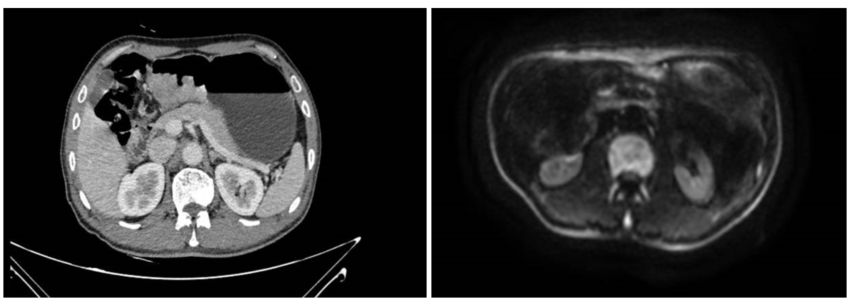

2024年8月8日上腹部增强CT及MR提示,胃体-胃角-胃窦部弥漫浸润性病灶,长径约87mm,最厚处约23mm,胃周小弯侧及大弯侧见多发淋巴结,较大者短径约7mm。未见明确远处转移征象(图1)。

图1.影像学检查(左:腹部CT;右:腹部MR)